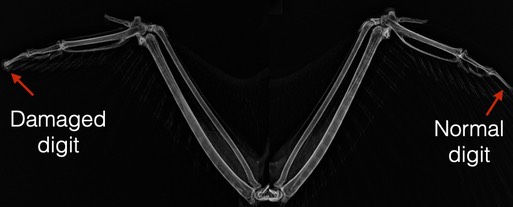

We don’t know how her feathers were broken, but radiographs showed bone damage to the very tip of her right wing.

She is now outside in a large flight pen where she can get out of the weather and feel safe. We will have to wait and see if she will be able to grow new feathers.